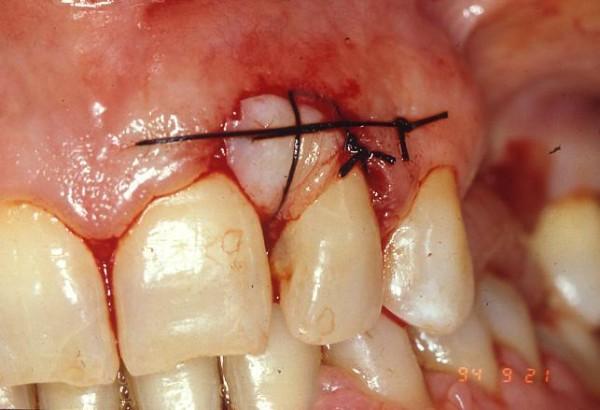

A total of 20 patients were enrolled and underwent initial, non surgical, periodontal treatment and training sessions on home oral hygiene training. The treatment plan involved radical exeresis of the mass followed by positioning of an autograft of connective tissue and keratinized gingiva.